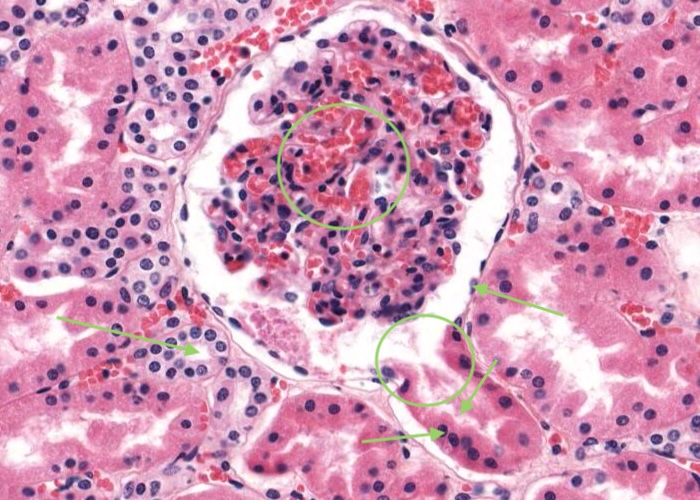

Interlobular arteries give off tiny afferent arterioles which run into the lobule to supply each renal corpuscle. An afferent arteriole enters a renal corpuscle, breaks up into a tuft of capillaries called a glomerulus, and then collects back into an efferent arteriole instead of a vein. This occurs at the "vascular pole". This is a nice image because it also shows part of a glomerulus with the urinary (tubular) pole visible (see more details in the next item). You may see an arteriole, but it will be impossible to tell whether it is afferent or efferent (although there is a slight hint that it is an afferent arteriole because it is adjacent to a distal convoluted tubule - ignore this though for now!). The efferent arteriole runs for only a short distance before breaking up into a second bed of peritubular capillaries, which nourish the proximal and distal tubules and absorb fluid. Even when these capillaries are collapsed you can easily see abundant red blood cells within their lumens between the convoluted tubules.

Besides the vascular pole (where the afferent and efferent arteriole enters or leaves the glomerulus; see previous item) each renal corpuscle has a urinary (tubular pole) where the proximal convoluted tubule originates. Note that the simple squamous epithelium of the parietal layer of the glomerulus (Bowman's) capsule abruptly changes to a simple cuboidal epithelium in the proximal convoluted tubule.